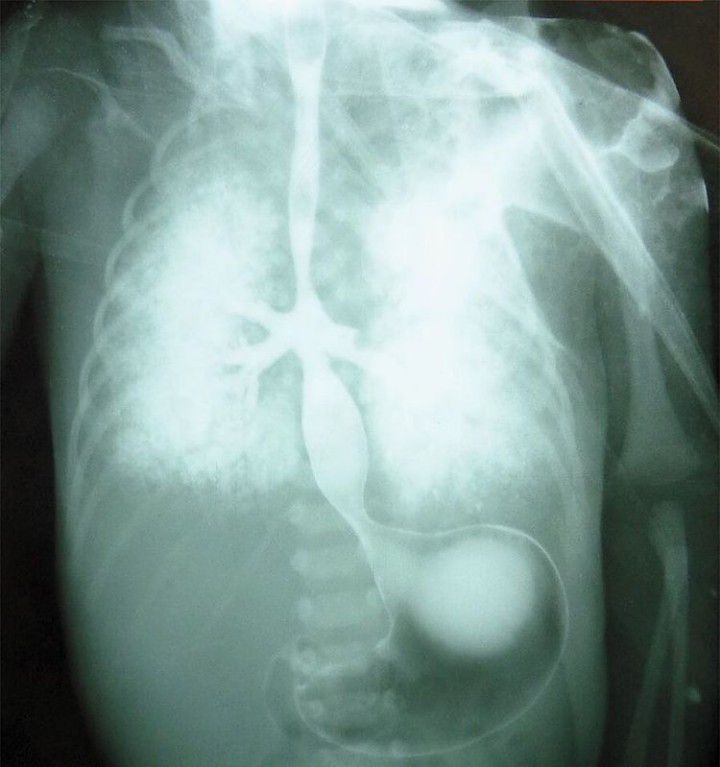

This is a case of Tracheal Agenesis with Bronchoesophageal Fistula. Cyanosis and respiratory distress developed in a neonate after delivery at 32 weeks of gestation. His mother had not received regular antenatal care. Endotracheal intubation and tracheostomy were attempted without success, and bag-valve–mask ventilation was performed, but the boy died from respiratory failure 4 hours after delivery. An esophagram obtained post mortem, after the administration of barium, suggested tracheal agenesis and bronchoesophageal fistula. An autopsy confirmed absence of the trachea, with fusion of the main bronchi and bronchoesophageal fistula, findings consistent with a diagnosis of type II tracheal agenesis, defined in accordance with the Floyd classification system. Additional findings included dysmorphic facial features, a double superior vena cava, an ostium secundum atrial septal defect, and a horseshoe kidney. Postnatal karyotyping revealed trisomy 18. Diagnostic advances, including those enabling assessment of the fetus on sonography and magnetic resonance imaging, have facilitated the establishment of this diagnosis prenatally. By: https://www.instagram.com/p/CaURZM5Mhjk/?igshid=YmMyMTA2M2Y=